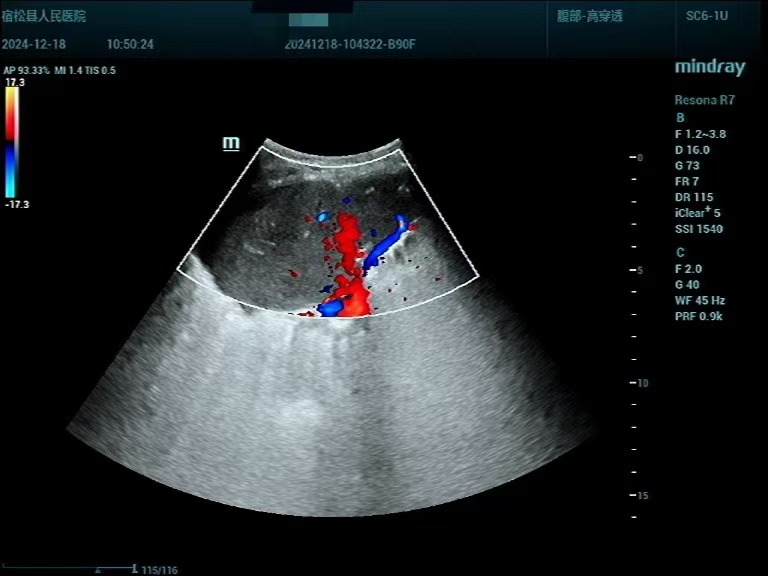

患者男性,83岁,发现肺部占位入院。其胸部CT提示右肺上叶肿块,纤支镜未能取到病理结果、建议进一步检查,呼吸内科评估后考虑肿块为恶性肿瘤的可能性大,需要进一步行活检以明确病理诊断。在征求家属意见后,超声诊断中心为其进行超声造影联合超声定位下肺肿块穿刺活检,该患者肺部病灶位于右肺上叶,结合不同频率超声探头检查,清晰显示了病灶内部结构及血流灌注情况。造影结束后,初步判断该肿物为恶性肿瘤的造影模式,在超声引导下,避开病灶大血管及坏死区,穿刺针取出肺部病变适量标本,活检病理结果提示鳞状细胞癌,为该患者的下一步诊治提供了充分依据。

▲常规超声表现:右肺上叶肿块

▲超声造影:右肺上叶团块超声造影符合肺Ca伴坏死表现

▲根据超声造影结果,超声引导下对活性病变组织取材